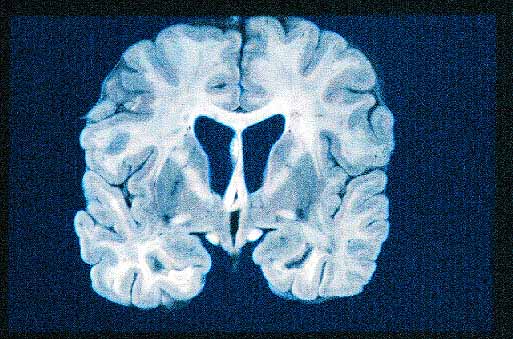

figura 1

Figura 1. Dilatación de los ventriculos cererbrales laterales. No se observa masa tumoral.